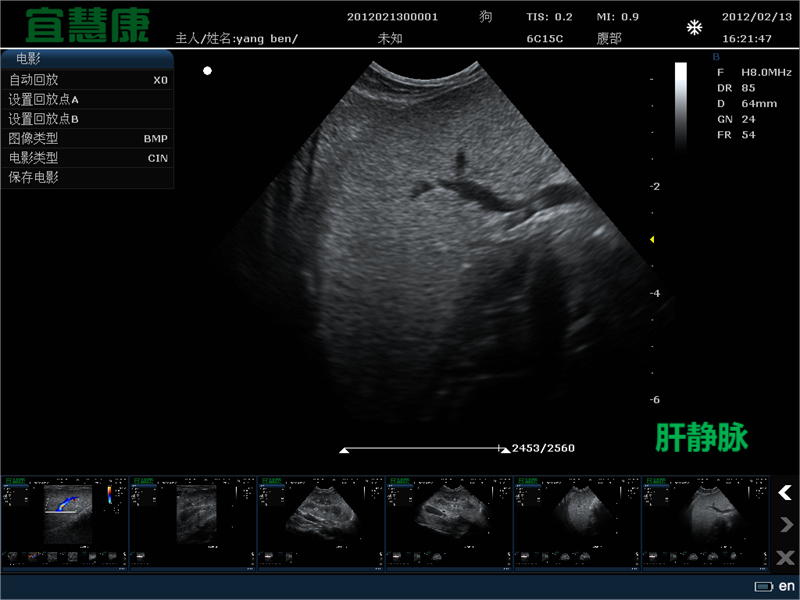

胸部的基本超声检查能够识别伪影,如:肺胸膜线、A线和B线。肺胸膜线是一条水平的高回声线,随着通气前后移动,可见于肋骨线以下。a线是肺胸膜线的人工复制,以明亮的水平线显示在胸膜深处。它们主要在正常的通气肺中可见。相反,在间质-肺泡水肿中可以看到B线(也称为超声肺火箭)。

它们是由超声波束在空气和液体之间的多次前后移动产生的,产生一个长的、垂直的强回声伪影,从胸膜线开始并向下延伸到屏幕,与呼吸同步地沿着胸膜线移动4].它们的出现是由于空气包围的肺组织中积聚了少量液体,产生了高阻抗梯度。它们的数量和宽度与病理的强度相关。

然而,B线不足以用于明确诊断,因为它们是由间质性肺泡液引起的,这可发生在心源性和非心源性肺水肿,以及急性呼吸窘迫综合征、各种病因的肺出血、肺炎、肺挫伤、肺肿瘤转移或肺纤维化中。评估B线的数量很重要,因为后续检查中更多的线将表明疾病的进展,而更少的线将证实治疗是有效的。单个B线可能是生理性的,然而更多的表示肺部病理。上述人工制品易于学习,这使得基本逻辑单元具有很高的可重复性——检查人员在B线检测中的一致程度根据他们的经验从92%到97%不等。